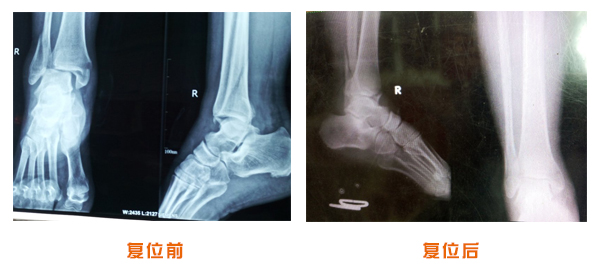

肥城市安駕莊梁氏骨科醫(yī)院是一所以梁氏手法正骨配合膏藥為特色的現(xiàn)代化??漆t(yī)院。

梁氏骨科術始創(chuàng)于清雍正年間,歷經(jīng)八代,至今已有三百年歷史。據(jù)1929年泰安縣志載“梁瑞圖先生,字增生,號蓮峰,安駕莊人,精岐黃并發(fā)明接骨,凡跌打車凡跌打車軋皮不破而碎骨者......【詳細】 |